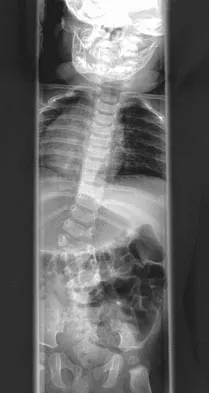

A 28-year-old man sustained a fracture-dislocation of T8 in a motor vehicle accident 1 week ago. The injury resulted in complete paraplegia. Management should consist of

With a complete injury in the thoracic spinal cord, the likelihood of neurologic recovery is small. If possible, treatment should be planned to allow rapid mobilization and rehabilitation without the use of braces and their associated skin problems. The use of long segment fixation provides for rapid mobilization without having to use braces postoperatively. The use of steroid protocol is controversial and should be considered only if it can be started within 8 hours of the injury. Laminectomy is contraindicated because it will increase instability.